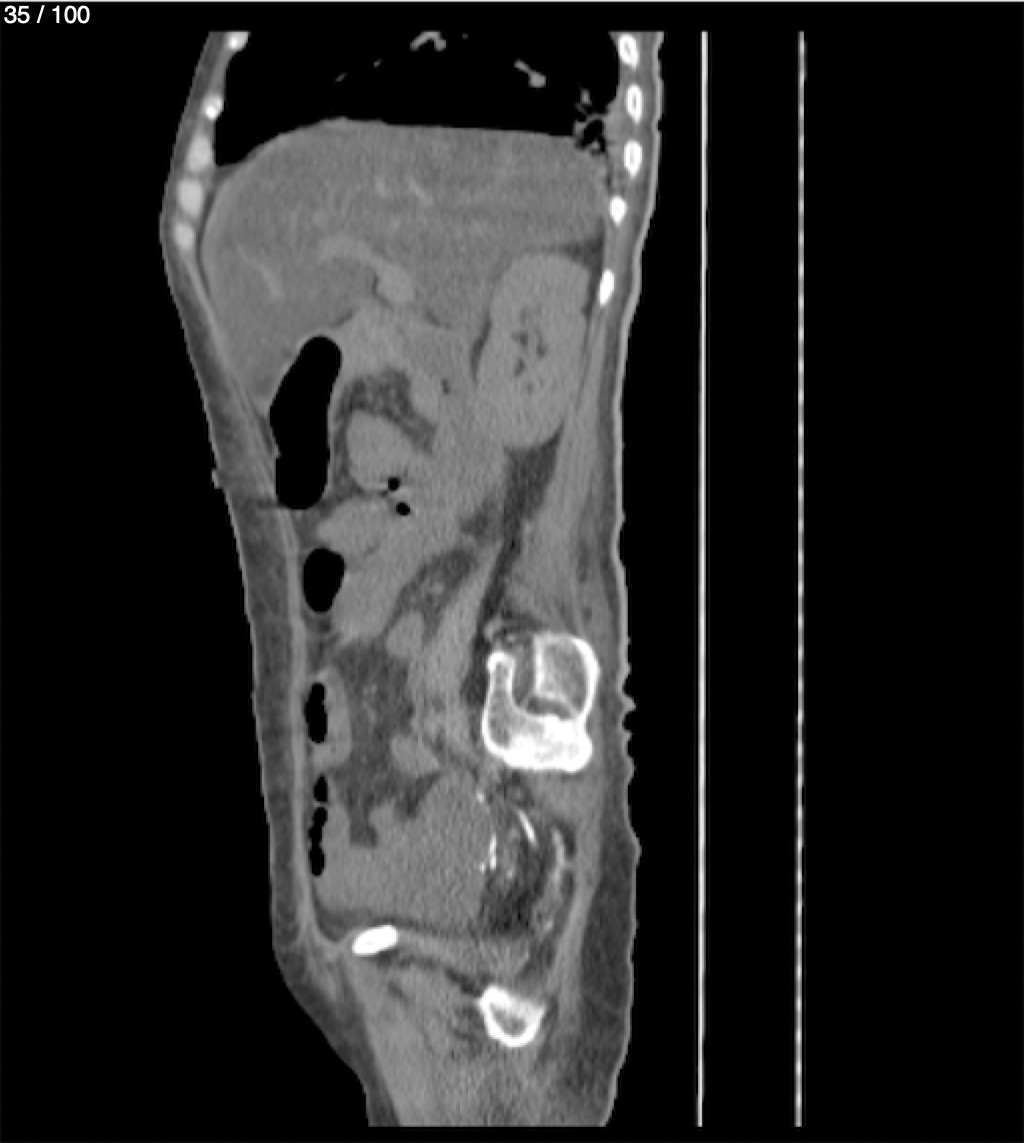

Hilda Geronimo Mendez 60A - T.C Abdomen Simple